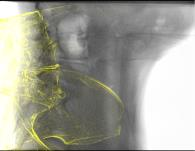

Deep Learning-based 2D/3D registration methods are highly robust but often lack the necessary registration accuracy for clinical application. A refinement step using the classical optimization-based 2D/3D registration method applied in combination with Deep Learning-based techniques can provide the required accuracy. However, it also increases the runtime. In this work, we propose a novel Deep Learning driven 2D/3D registration framework that can be used end-to-end for iterative registration tasks without relying on any further refinement step. We accomplish this by learning the update step of the 2D/3D registration framework using Point-to-Plane Correspondences. The update step is learned using iterative residual refinement-based optical flow estimation, in combination with the Point-to-Plane correspondence solver embedded as a known operator. Our proposed method achieves an average runtime of around 8s, a mean re-projection distance error of 0.60 $\pm$ 0.40 mm with a success ratio of 97 percent and a capture range of 60 mm. The combination of high registration accuracy, high robustness, and fast runtime makes our solution ideal for clinical applications.